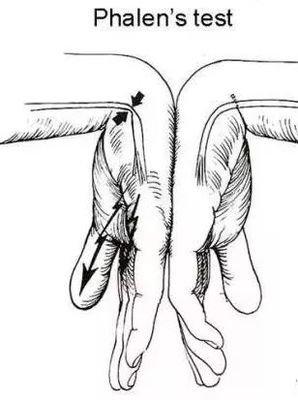

手根管症候群のテスト。手首を曲げて手の甲をぎゅっと手の甲に当ててみて、しびれの方が強ければ、基本的に手首が詰まっています。